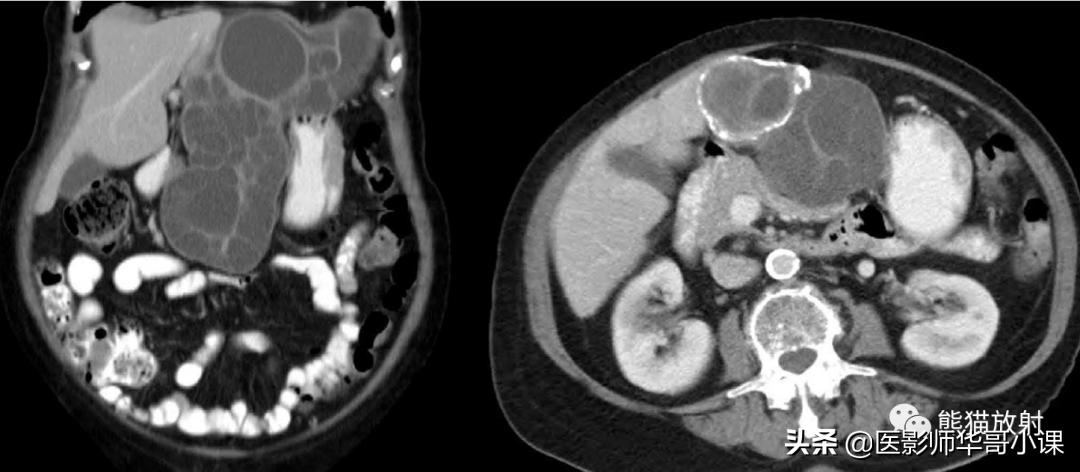

包虫病主要是感染细粒棘球绦虫所致。腹膜包虫病常常由于肝包虫病外伤或手术破裂而发生。 腹膜出现囊状占位性病变,囊壁薄,常有分隔 。腹膜种植时CT是首选检查方法(图)。边缘环形钙化具有提示诊断意义。

腹膜包虫病。增强CT显示一个大而多分隔的囊性腹膜肿块。囊内见子囊,多发分隔的蜂窝状表现,边缘钙化为其特征性表现。